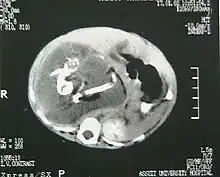

A fetus in fetu can be considered alive, but only in the sense that its component tissues have not yet died or been eliminated. Thus, the life of a fetus in fetu is akin to that of a tumor in that its cells remain viable by way of normal metabolic activity. However, without the gestational conditions in utero with the amnion and placenta, a fetus in fetu can develop into, at best, an especially well differentiated teratoma; or, at worst, a high-grade metastatic teratocarcinoma. In terms of physical maturation, its organs have a working blood supply from the host, but all cases of fetus in fetu present critical defects, such as no functional brain, heart, lungs, gastrointestinal tract, or urinary tract. Accordingly, while a fetus in fetu can share select morphological features with a normal fetus, it has no prospect of any life outside of the host twin. Moreover, it poses clear threats to the life of the host twin on whom its own life depends.[4]

Fetus in fetu may be a parasitic twin fetus growing within its host twin. Very early in a monozygotic twin pregnancy, in which both fetuses share a common placenta, one fetus wraps around and envelops the other. The enveloped twin becomes a parasite, in that its survival depends on the survival of the host twin, by drawing on the host twin's blood supply. The parasitic twin is anencephalic (without a brain) and lacks some internal organs, and as such is unable to survive on its own. As the host twin has to "feed" the enveloped twin from the nutrients received over a single umbilical cord, they usually die before birth.